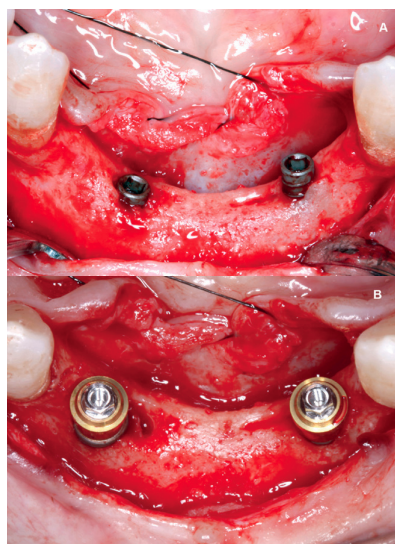

Aft er 4 years, the second and third quadrant molars began to have excessive mobility and serious periodontal problems, so it was decided to remove them and regenerate the alveoli with PRGF-Endoret. Once the area was regenerated (a month and a half later), a conebeam was performed to evaluate the residual bone volume. It can be seen how there was an uneven bone crest with areas of 3.3 mm in height up to a maximum of 7 mm (Figures 9 and 10). On this occasion, due to the protocol change described above, we opted for the direct insertion of extra-short implants, since the surgical protocols to address this type of situation in 2011 varied substantially, with these implants being a first-line tool for the treatment of this type of atrophy (Figure 11). Two extra-short implants were selected (5.5 mm diameter x 6.5 mm length for tooth 26, and 6 mm diameter x 5.5 mm length for tooth 27).

Back in 2007, the therapeutic protocol for these cases was very different (Figures 5-7), with short implants without full development – and without studies demonstrating the importance of diameter over implant length – efforts were focused on the search for anchorage by implant length instead of looking for the bicortical (vestibular-lingual) stability that short and wide implants perform. During this ti me, the failure of molars 46 and 47 also occurred; these were also extracted and replaced with dental implants.